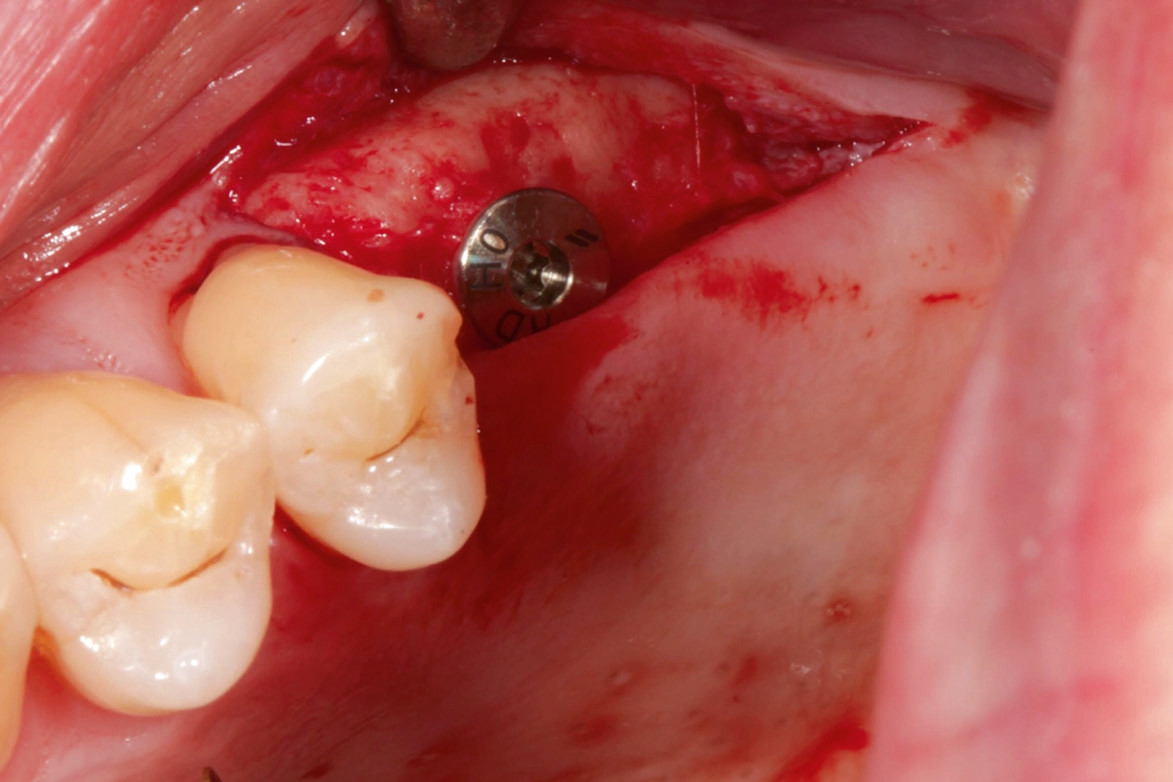

Nach lokaler Anästhesie wurden ein Kieferkammschnitt und eine nur minimale Mobilisation des Mucoperiostlappens durchgeführt. Beim internen Sinuslift nach Summers wird die Pilotbohrung bis ca. 1 mm vor die Begrenzung der Kieferhöhle vorgenommen und je nach Knochenangebot und Qualität mittels verschiedener Osteotome (Institut Straumann) weiter aufbereitet. Unabdingbar ist dabei die regelmäßige Kontrolle der Unversehrtheit der Schneider‘schen Membran durch einen „Nasenblasversuch“. Nach erfolgreicher Aufbereitung des Lagers konnte ein Implantat Größe 4,1/10 mm sehr gut primärstabil inseriert werden, anschließend primärer Wundverschluss mittels 5/0 monophiler Naht. Nach vier Monaten erfolgte die minimalinvasive Freilegung und Applikation des Gingivaformers.